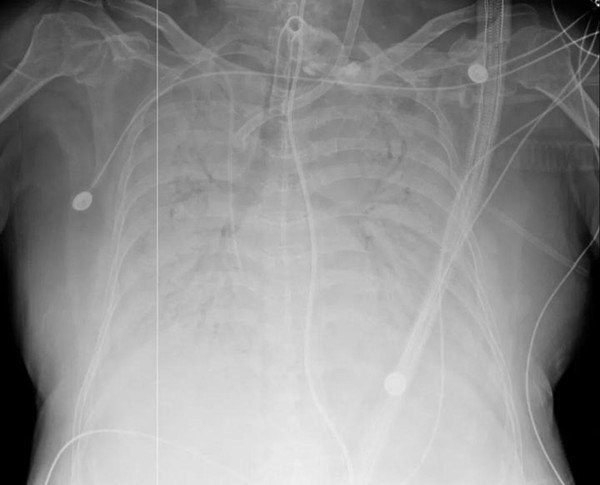

術前

依靠人工膜肺(ECMO)勉強維持生命的患者,已脆弱得經不起半點風險,能否經受肺移植手術?手術方案經過反復再反復討論。

我國知名器官移植專家、浙大一院黨委書記梁廷波帶領相關科室最權威的專家在每天兩次的MDT會診中,針對患者的相關檢查數據反復評估病情、制定治療方案。移植通過了醫院大器官移植倫理委員會的論證,并得到了患者家屬的知情同意,他們表示:堅決要做,信任醫生!

實際上,手術難度超乎想象:一方面患者呼吸衰竭導致肺動脈壓力增高,右心明顯增大,整個心臟旋轉,增加手術操作難度,另一方面體型肥胖,盡管本身沒有基礎疾病,但由于胸腔小,空間與肺的大小不匹配,造成心血管功能較普通人脆弱,這不僅是導致其病情迅速進展的因素之一,也使移植手術更加復雜。

但經過專家組評估,患者生病前身體健康,心肺功能也都正常,主要是由于新冠肺炎進展導致病情迅速惡化,病況符合相關手術標準。